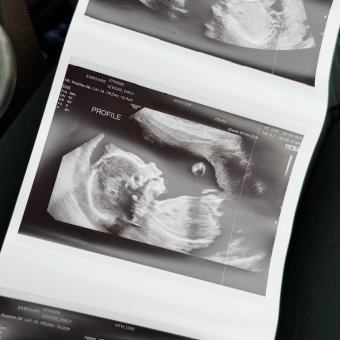

Emily Sevigne & David Kida

East Brookfield, MA

July 2026